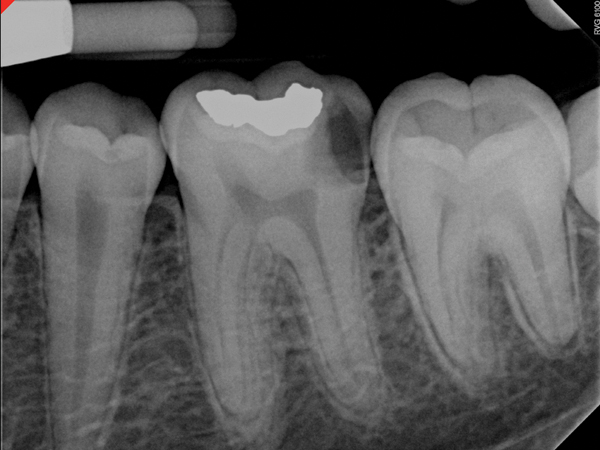

Fig 4. and Fig 5. Before and after radiographs of bioceramic sealer hydraulically moved with the gutta-percha point. Note that the cold hydraulic technique results in lateral canal “puffs” similar to the warm vertical technique. Courtesy of Dr. Gilberto Debelian.

Figure 4

Figure 5